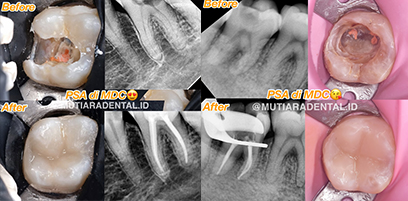

PSA (Root Canal Treatment)

Prosedur kedokteran gigi untuk membersihkan dan mengisi bagian dalam gigi yang berisi saraf dan pembuluh darah (pulpa) yang terinfeksi atau rusak, bertujuan untuk menyelamatkan gigi dari pencabutan dan mempertahankan fungsinya. Perawatan ini menghilangkan jaringan pulpa yang sakit, mengatasi nyeri, dan mencegah infeksi menyebar.